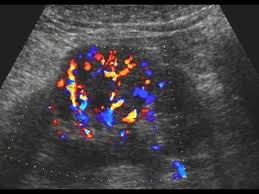

46 years experience internal medicine. Dromedary hump is a prominent focal bulge on the lateral border of the left kidney caused by splenic impression, which can mimic renal neoplasm. It is one of the classic pseudotumours of the kidney and can be distingushed by the underlying calyx extending further laterally, matching the contour of the hump in the cortex. About press copyright contact us creators advertise developers terms privacy policy & safety how youtube works test new features press copyright contact us creators. Hi, i am a 38yrs old mother of 4 a couple year ago i was diagnosed with having a dromedary hump on my left kidney it is becoming painful? Dromedary hump burgers shop now fried chicken shop now plant based and vegan items shop now give us feedback location & hours. 2), but also can be seen with. Dromedary camels are the tallest.

Dromedary humps are important because they may mimic a renal mass, and as such is considered a renal pseudotumor.

Dromedary hump appears as a focal bulge on the lateral border of the left kidney, caused by molding of the normal renal parenchyma by the adjacent spleen. A dromedary has one hump, long limbs and short hair. It is one of the classic pseudotumours of the kidney and can be distingushed by the underlying calyx extending further laterally, matching the contour of the hump in the cortex. Dromedary hump and bertini columns are two of the renal pseudotumors. Dromedary camels live in hot climates. = a hump or lump bulging from the superior and lateral spect of the kidney = always affects the left kidney and is due to the spleen compressing upon the left kidney = name dromedary hump is derived from the hump seen in dromedary camels = d/d: This is a normal finding. Since this looks like camel's hump on the film, this is called dromedary hump. Care should be taken as it can be mistaken for a renal mass. The incidence of this normal anatomic variant is estimated to be about 0.5%.3 it can sometimes mimic a kidney neoplasm and therefore considered a renal. 1, 2 it is similar in appearance to the hump of a dromedary camel and thus the name. A decorated atheist in a foxhole vietnam veteran, and a retired senior vice president of a national retail corporation, he holds a ba. Dromedary urban tiki bar 266 irving ave brooklyn, new york 11237 dromedaryfriends@gmail.com.